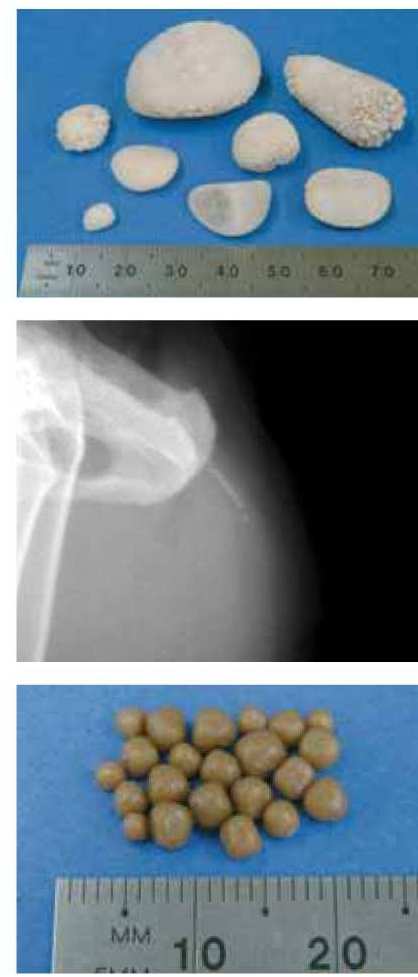

Камни образуются в результате отклонений внутренней среды от нормы. При рН мочи большой кислотности и слишком высоком содержании кальция образуются рыхлые оксалаты. У них пористая структура и острые края. При ощелачивании — струвиты. Предпосылки к их образованию. — избыток в корме фосфора и магния. В обоих случаях нарушение имеет хронический характер, лечится консервативным и хирургических путем, требует постоянного наблюдения и коррекции терапии питомца для обеспечения его хорошего самочувствия.

В зависимости от типа солей, оседающих в почках или мочевом пузыре, у животных формируются разные виды конкрементов. Наиболее распространенные мочевые камни — это оксалаты и струвиты. На них приходится около 90% всех конкрементов. Остальные 10% — это ураты, цистины, ксантины и т. д.

Каждый тип камней формируется при разных условиях, например, струвиты образуются в щелочной среде и при переизбытке минералов, предшественников камней (таких как фосфор и магний), а оксалаты, напротив, образуются в подкисленной среде и при повышенном количестве выводимых с мочой кальция и щавелевой кислоты.

Камни в мочевом пузыре, также известные как «уролиты», представляют собой каменистые скопления минералов, кристаллов и органических материалов, которые накапливаются в мочевом пузыре. Люди могут получить их, но и ваша кошка тоже. Они возникают в результате какого-то воспаления или заболевания. Эти камни могут оставаться маленькими у кошек или могут вырасти до нескольких миллиметров в диаметре или больше. Камни могут тереться о стенки мочевого пузыря, вызывая воспаление и боль.

Камни мочевого пузыря также могут закупорить мочеиспускательный канал и затруднить или даже сделать невозможным мочеиспускание вашей кошки. В зависимости от минералов, входящих в состав камня, его форма и размер будут различаться.

Двумя наиболее распространенными типами камней мочевого пузыря являются струвитные и оксалатно-кальциевые камни.

Камни мочевого пузыря, или уролиты, представляют собой просто организованные скопления затвердевших минералов, обнаруживаемые в моче. Они могут возникать в любом месте мочевыводящих путей, от почек до уретры — узкой трубки, по которой моча выводится из мочевого пузыря наружу.

Камни разных размеров. У вашей кошки может быть крошечный камень или камень размером с мочевой пузырь. Камни также различаются по форме и цвету. Они могут быть гладкими или иметь неровные края. Камни создают проблемы, потому что они могут повредить окружающие ткани, вызвать воспаление, образование рубцовой ткани и предрасполагать кошку к инфекции, особенно если они имеют шероховатые или неровные края.

Камни из оксалата кальция

Камни из оксалата кальция являются наиболее распространенными мочевыми камнями у кошек, согласно Ветеринарному руководству компании Merck. Они чаще всего наблюдаются у кошек среднего и старшего возраста. К породам, наиболее склонным к развитию камней из оксалата кальция, относятся рэгдолл, британская короткошерстная, экзотическая короткошерстная, гималайская, персидская и шотландская вислоухая. Камни из оксалата кальция могут образовываться в чрезмерно кислой моче. Их можно увидеть у кошек с повышенным уровнем кальция в крови и моче вследствие состояния, называемого идиопатической гиперкальциемией, или у кошек с хроническим заболеванием почек.